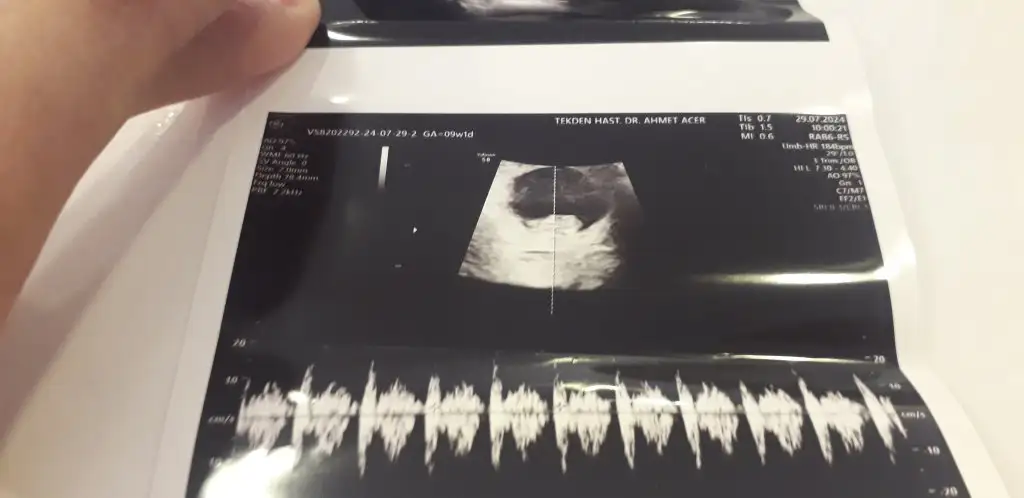

Bizim de bakar mısınız 10+1 bugün

• IMG_1404.webp

IMG_1404.webp

28,6 KB · Görüntüleme: 66

• IMG_1405.webp

IMG_1405.webp

41,6 KB · Görüntüleme: 69